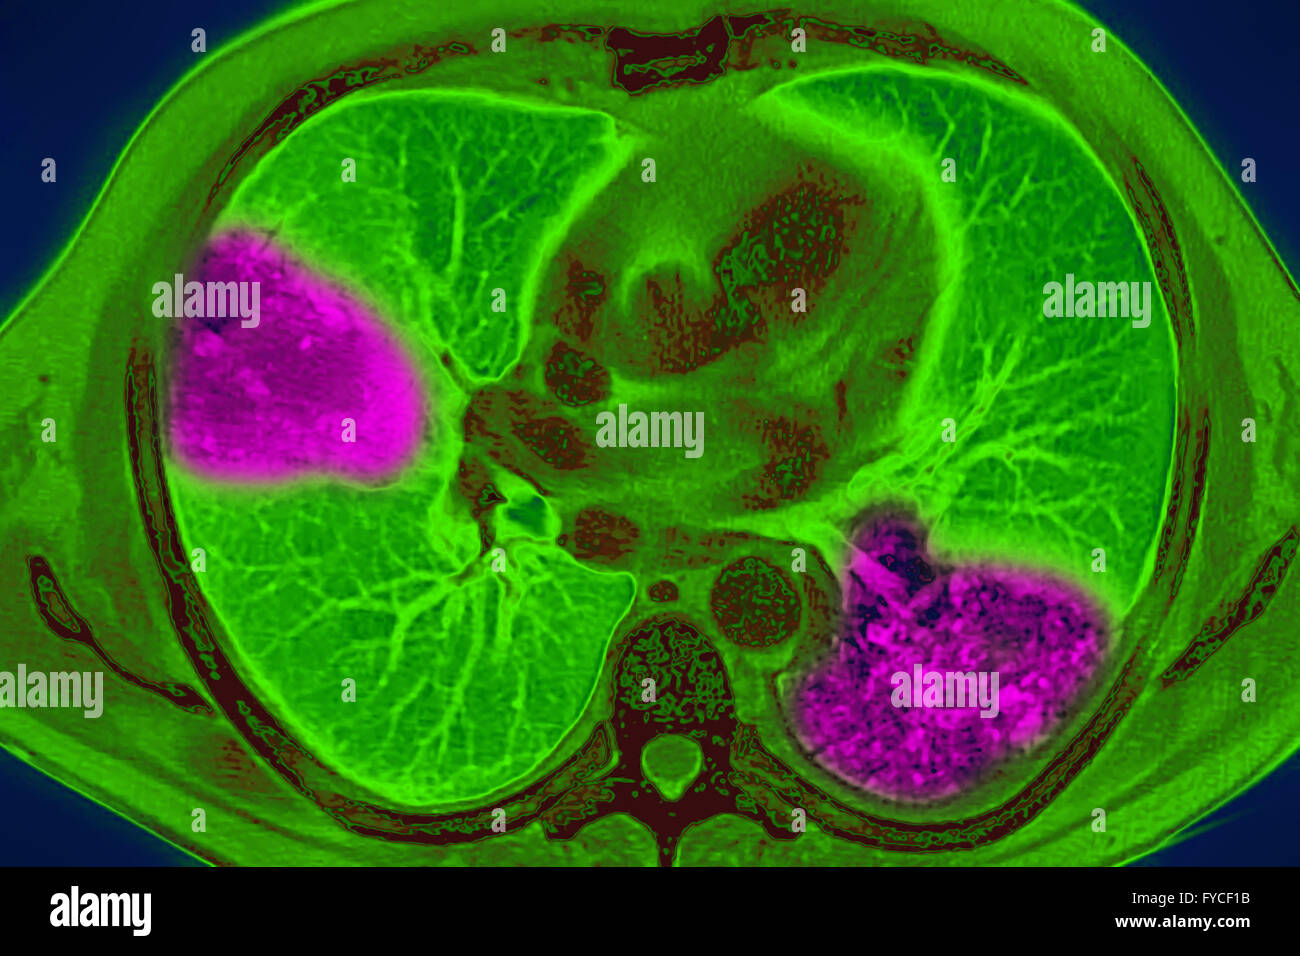

RM2RF8HPX–Pneumonie du poumon droit (infection respiratoire aiguë) révélée par une radiographie thoracique frontale.

RM2RF8HR9–Pneumonie du poumon droit (infection respiratoire aiguë) révélée par une radiographie thoracique frontale.

RM2RF8HPN–Pneumonie du poumon droit (infection respiratoire aiguë) révélée par une radiographie thoracique frontale.